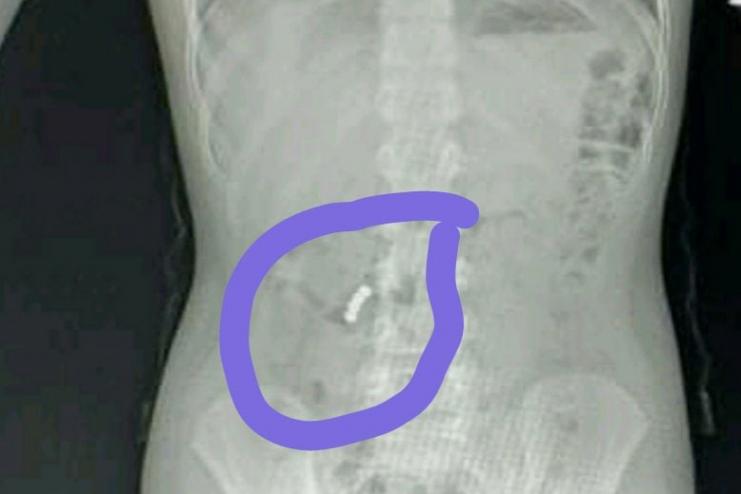

Четвероклассник из Черноморской ООШ №2 умудрился съесть сразу четыре небольших (но мощных) элемента. Они застряли в желудке и, склеиваясь, начали пережимать и разрывать внутренние органы. Пострадавшего срочно госпитализировали, ему понадобится операция и долгая реабилитация.